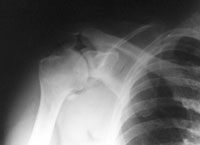

Ein 44-jähriger Patient ist auf dem ersten Eis des Winters ausgerutscht und auf die rechte Schulter gestürzt.

Er klagt über starke Schmerzen im Bereich der rechten Schulter und ein Instabilitätsgefühl im Gelenk. Die Beweglichkeit des Arms ist aufgrund der Schmerzen eingeschränkt, Durchlutung und Sensibilität sind normal.

linke Schulter pa

Welche Befunde liegen vor (mehrere richtige Antworten möglich)?